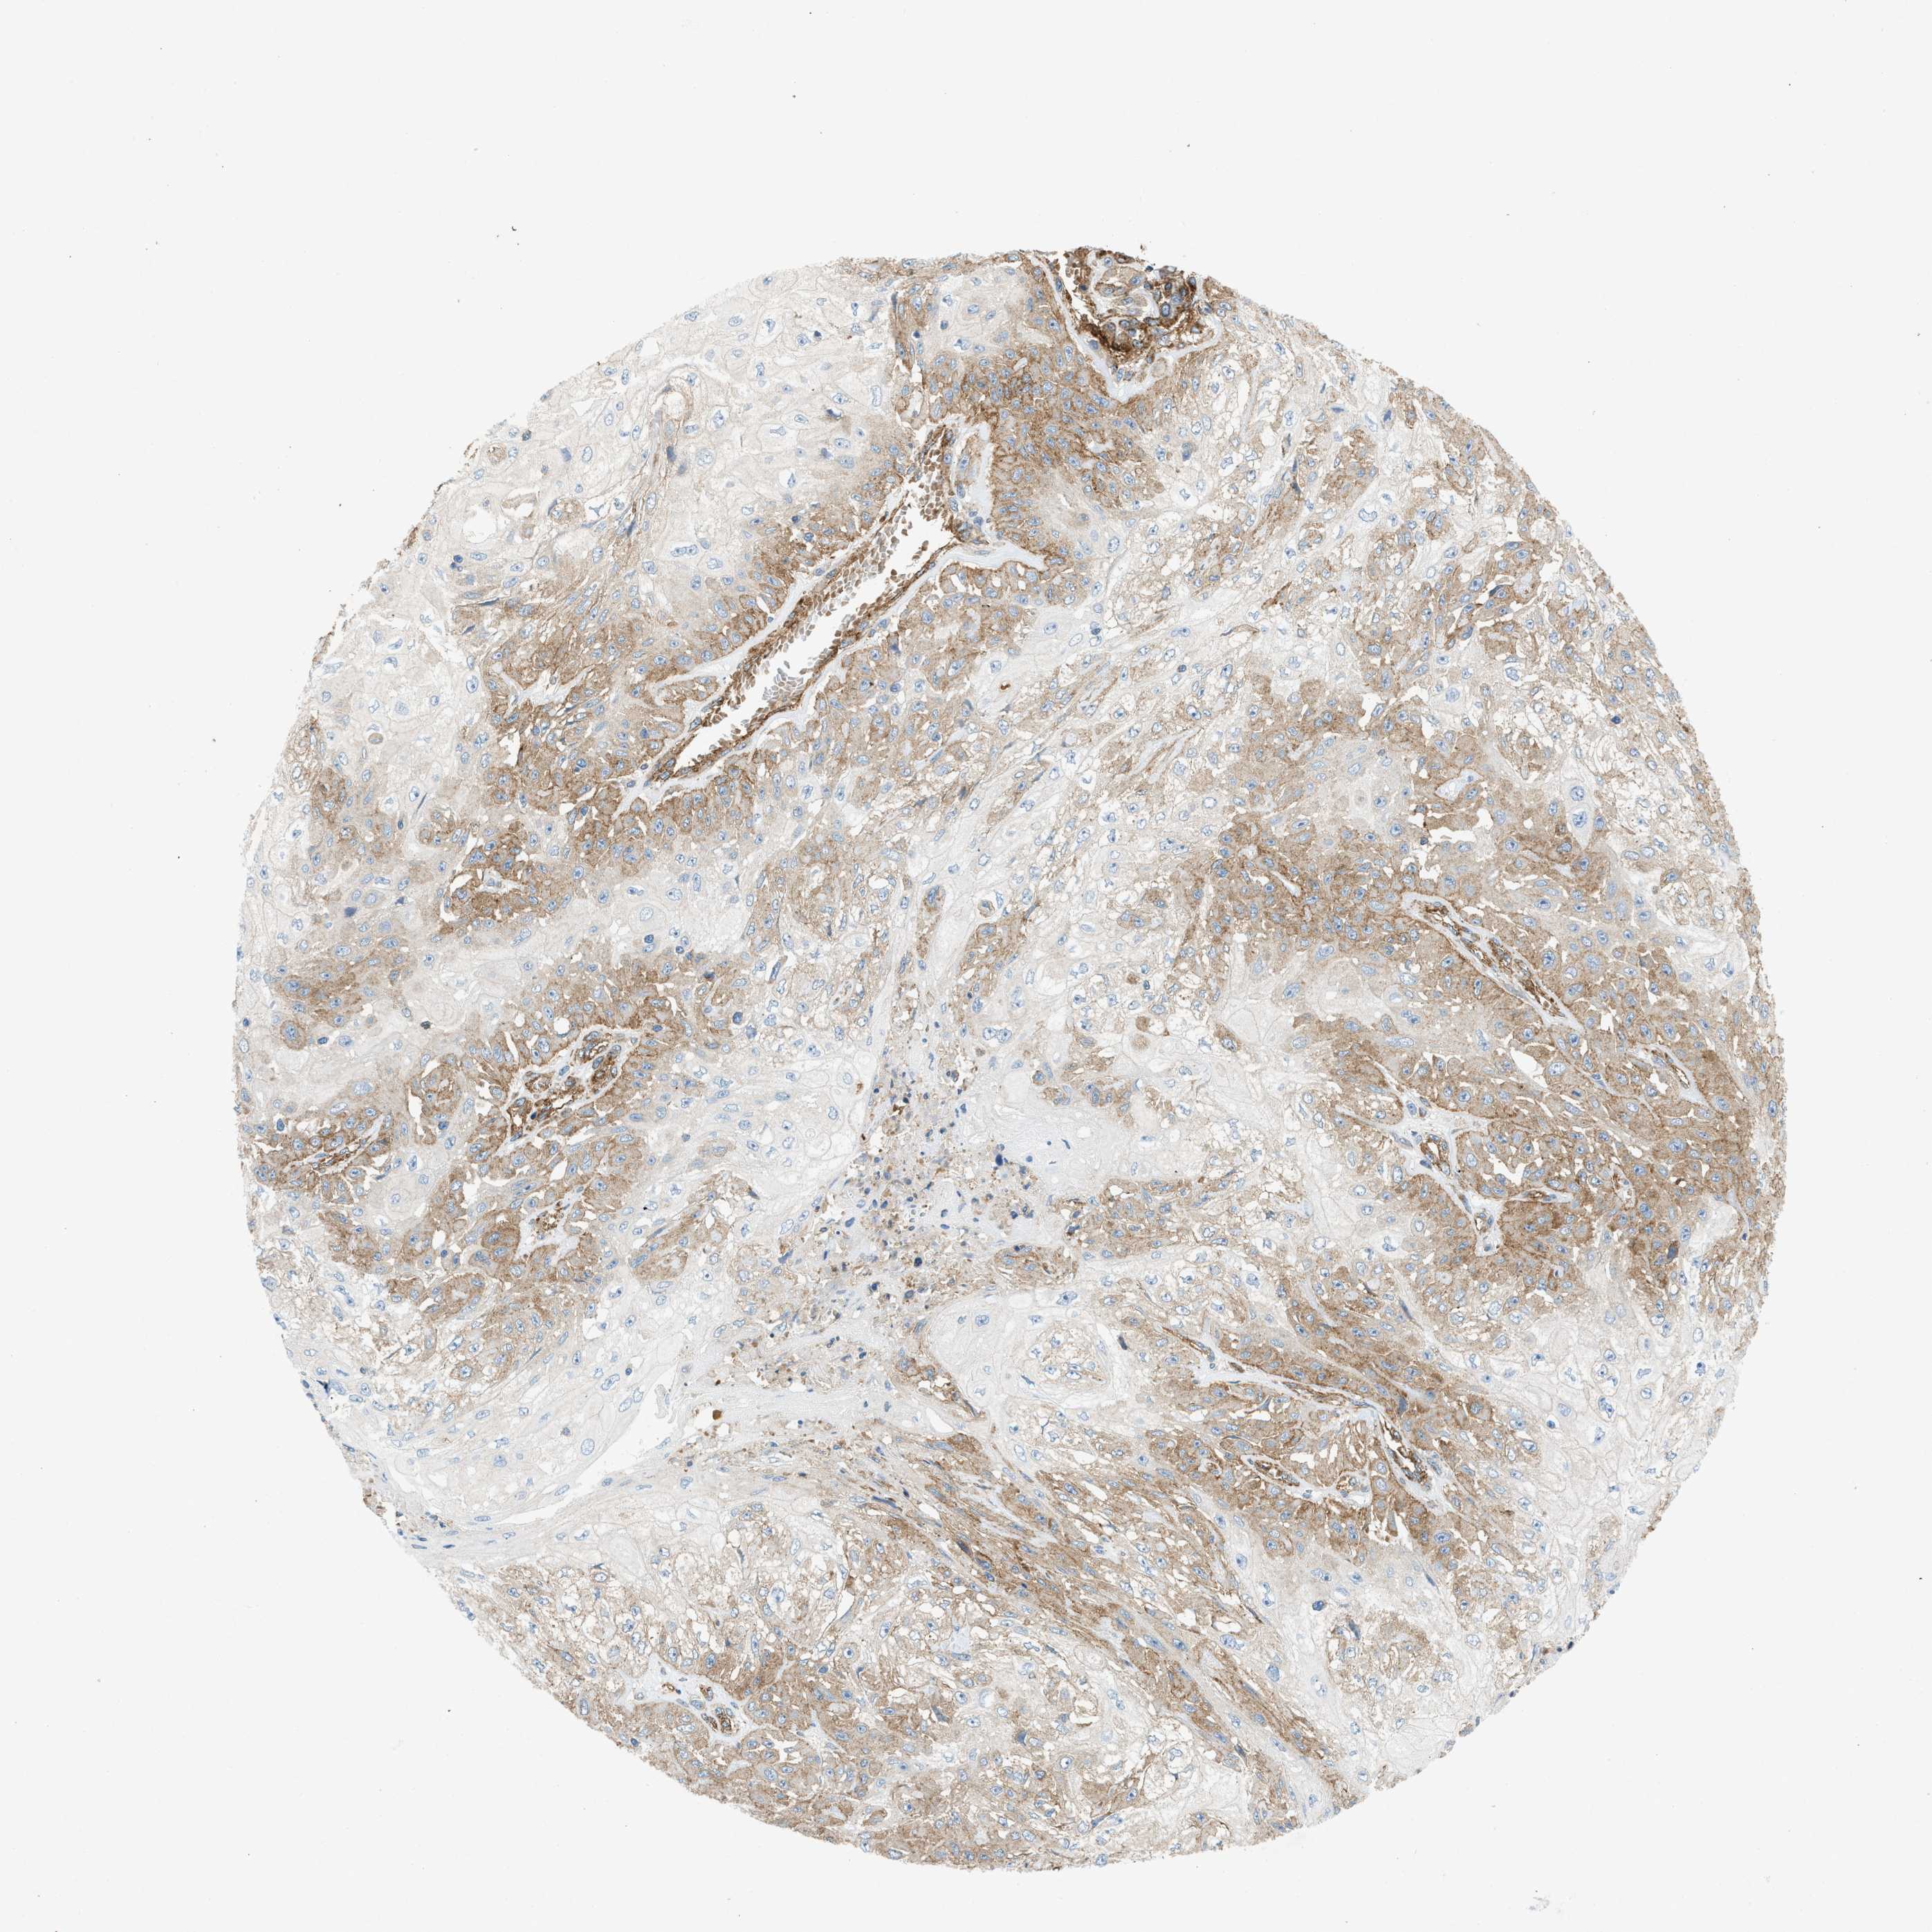

SKIN CANCER - Protein expressioni

A mouse-over function shows sample information and annotation data. Click on an image to view it in a full screen mode. Samples can be filtered based on level of antibody staining by selecting one or several of the following categories: high, medium, low and not detected. The assay and annotation is described here.

Antibody stainingi

Antibody staining in the annotated cell types in the current human tissue is reported as not detected, low, medium, or high, based on conventional immunohistochemistry profiling in selected tissues. This score is based on the combination of the staining intensity and fraction of stained cells.

Each image is clickable and will lead to virtual microscopy that enables deeper exploration of all samples and also displays staining intensity scores, fraction scores and subcellular localization as well as patient and tissue information for each sample.

Antibody HPA013606

Antibody HPA017964

Antibody CAB015334

Antibody CAB016402

Staining

High

Medium

Low

Not detected

Intensity

Strong

Moderate

Weak

Negative

Quantity

>75%

75%-25%

<25%

None

Location

Nuclear

Cytoplasmic/membranous

Cytoplasmic/membranous,nuclear

Squamous cell carcinoma in situ, NOS

Squamous cell carcinoma, NOS

Squamous cell carcinoma, metastatic, NOS

Basal cell carcinoma

Adnexal tumor, benign